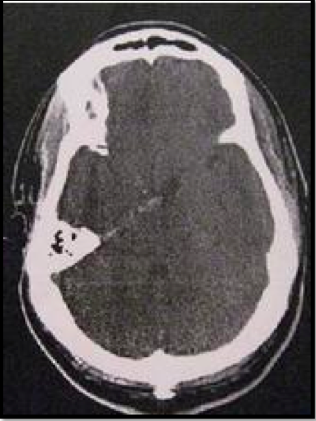

Seorang laki-laki usia 38 tahun dengan riwayat 2 hari sakit kepala parah, fotopobia, dan emesis. Hasil pemeriksaan pasien secara neurologik intak. hasil CT digambarkan di bawah ini. Hal apa yang TIDAK perlu dilakukan pada pengelolaan entitas ini?

A. Angiografi

B. Pemantauan Jantung

C. Pemantauan Elektrolit

D. Terapi Hiperdinamis

E. Pemantauan Hidrosepalus

E